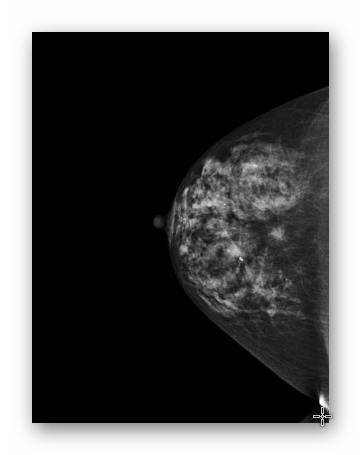

SUTEK PRAWIDŁOWY

MAMMOGRAFIA